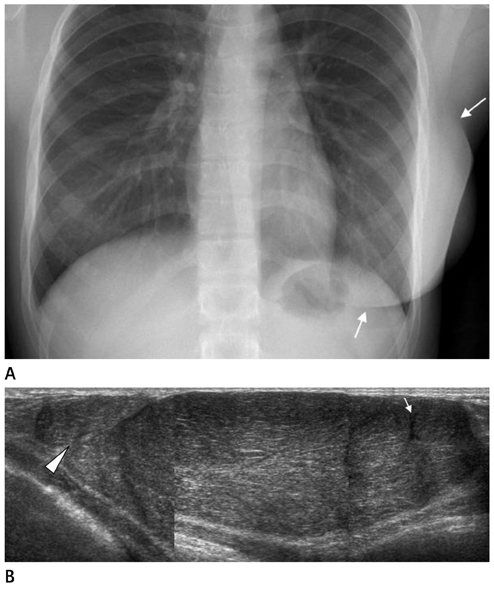

- The purpose of this study is to review various breast diseases in children and adolescents and to illustrate the sonographic findings. We reviewed the cases at our institution in order to identify breast disease in children and adolescent patients who underwent sonography and mammography. Breast disease in children and adolescents included developmental disturbance, infection, benign tumors and inherent defects. In contrast to adults, the radiologic findings of malignant breast conditions in pediatric populations have rarely been reported; however, we show ductal carcinoma in situ with juvenile fibroadenoma and rhabdomyosarcoma. During childhood and adolescence, the recognition and correct identification of physiologic breast development and specific lesions in breast entities on radiologic findings is most helpful in identifying and characterizing abnormalities and in guiding further investigation.